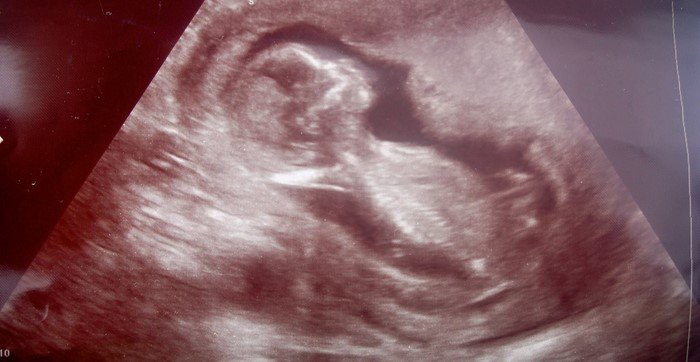

Супруги решили применить тот же метод еще раз. Но спустя каких-то четыре дня после того, как Каролин забеременела, в доме Сэвиджей раздался телефонный звонок.

Врач в ужасе сообщил мужу и жене, что случилась страшная ошибка. В ходе процедуры женщине «подсадили» другой зародыш. Так Каролин, сама того не желая, оказалась в роли суррогатной матери.

Почувствовав знакомые симптомы, Каролин на всякий случай купила тест на беременность. Результат сразил ее наповал.

Медики, утверждавшие о бесплодии, оказались неправы. Спустя несколько выкидышей и множество лечебных процедур мать пятерых детей оказалась способна забеременеть естественным способом!

К удивлению врачей, наблюдавших за состоянием здоровья 45-летней беременной, женщина выносила малыша без каких-либо осложнений. Крохотный Николас Уинтон Сэвидж появился на свет в положенный срок. Обследовавшие мальчика специалисты констатировали: ребенок оказался абсолютно здоров.